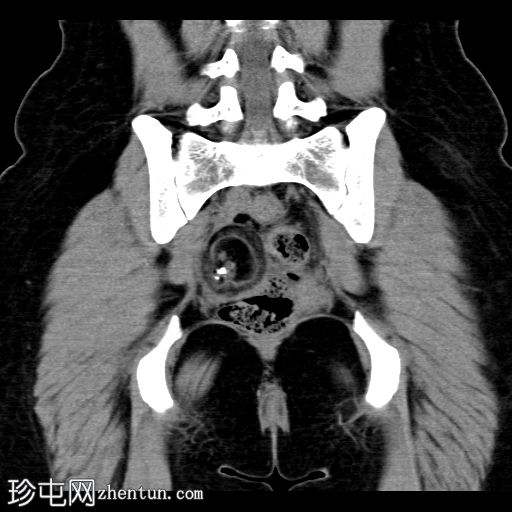

CT扫描

轴向扫描

非造影扫描

冠状扫描

盆腔内可见巨大脂肪密度肿块,伴有牙齿。